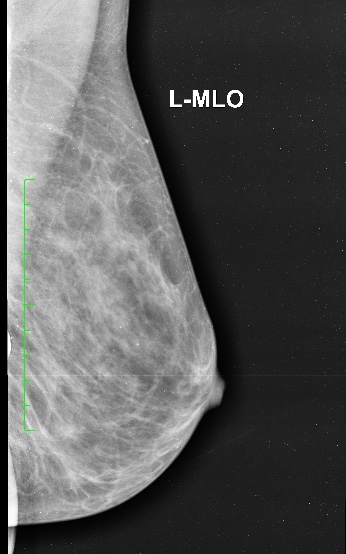

Conventional Xray Mammography It has become widely acceptable method for screening of women after certain age for early detection of malignant and pre malignant conditions of breast.

It is a non invasive technique for quantification of radioactivity after injection of radioactive substance in the body. it has various clinical applications especially oncologic imaging for diagnosis, staging and follow up for treatment response in cancer patients.

Non- oncologic applications are emerging gradually in cases of dementia and other neurological conditions.

Conventional Xray Mammography It has become widely acceptable method for screening of women after certain age for early detection of malignant and pre malignant conditions of breast.